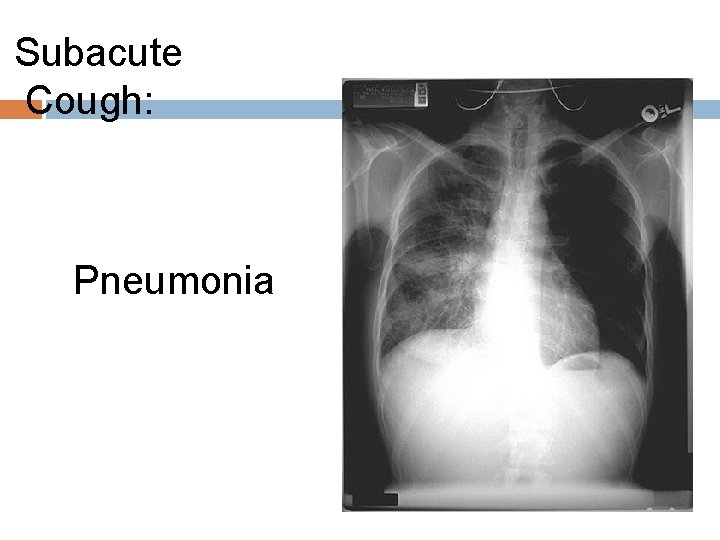

Subacute Cough: Pneumonia